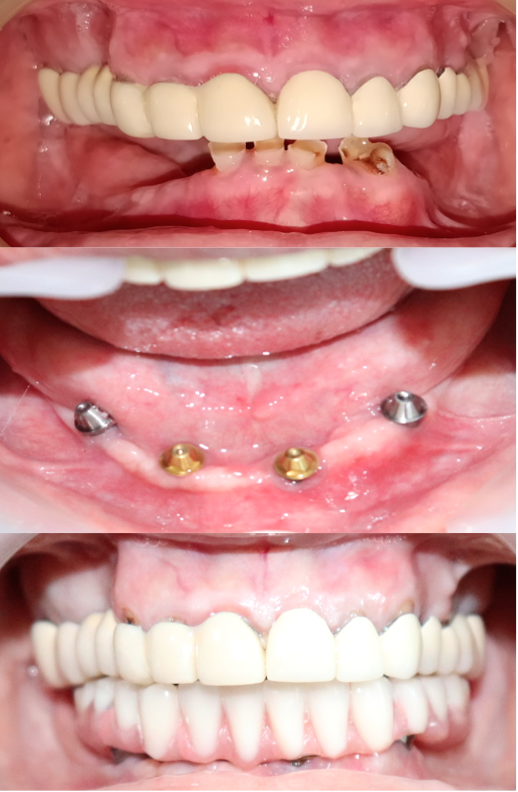

Full Mouth Rehabilitation

Card image